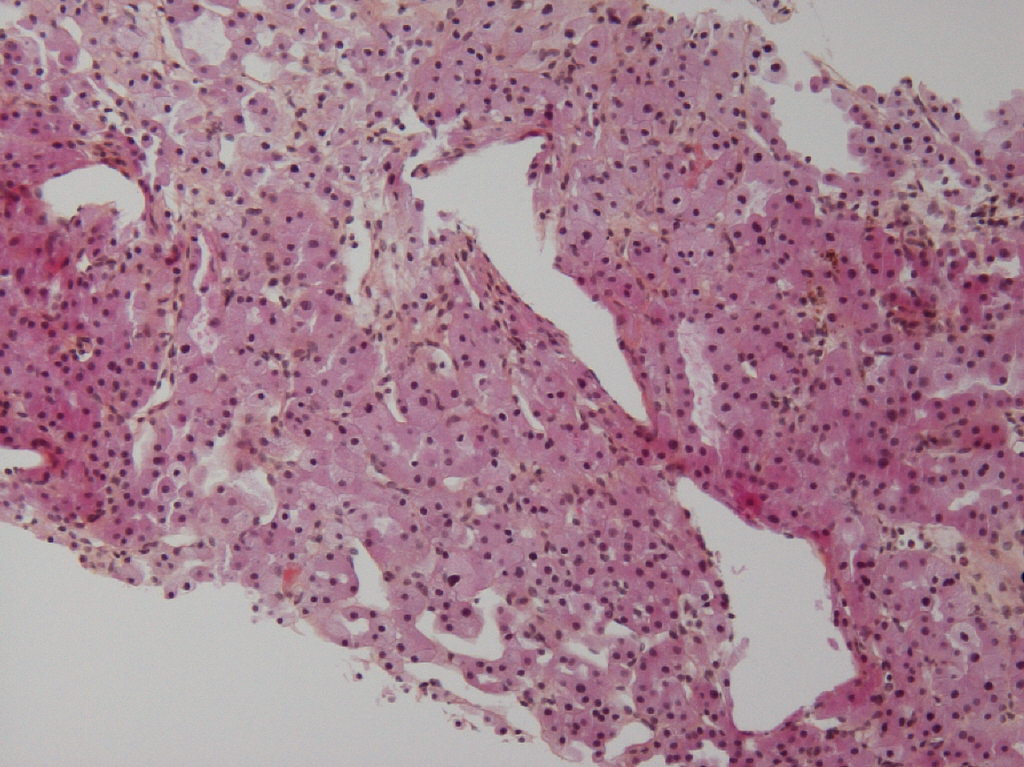

Case ID: 615

Consensus grade: I would not grade this tumor

Case description (by case creator):

oncocytoma biopsy